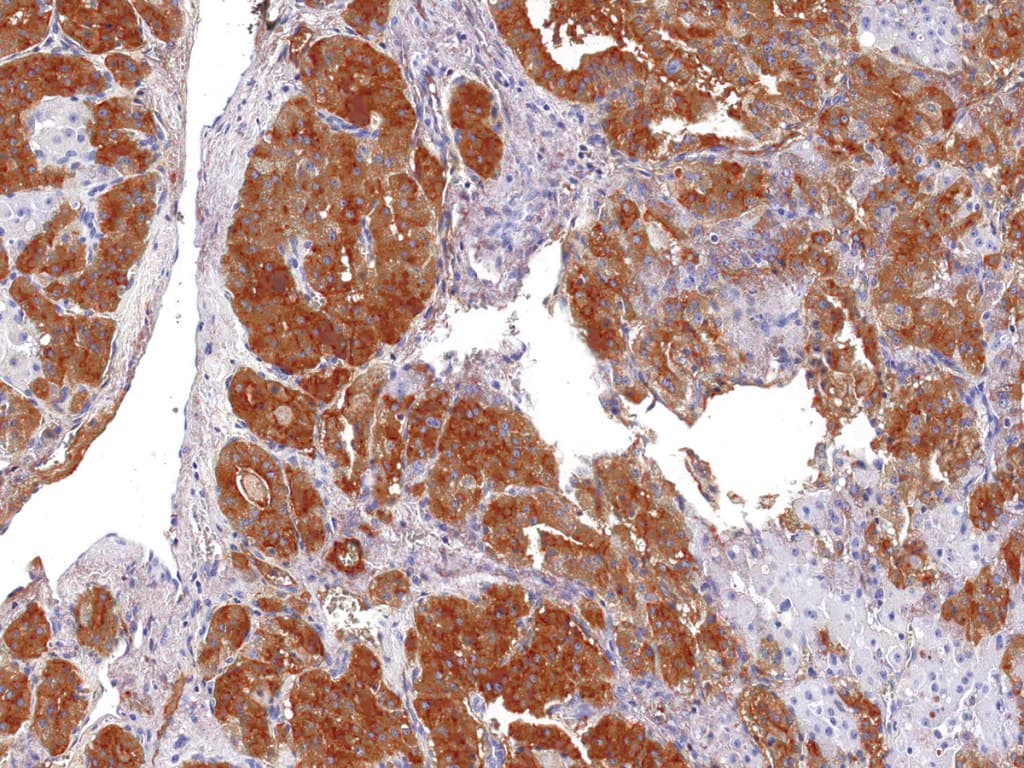

Quase todos os carcinomas foliculares da tiróide mancham a tiroglobulina e por vezes produzem um padrão de coloração focal. Pelo contrário, os carcinomas mal diferenciados e os adenocarcinomas não-tiróides não coram para a tiroglobulina, pelo que o anticorpo da tiroglobulina é um instrumento de diagnóstico útil para o reconhecimento de carcinomas papilares e foliculares da tiróide. Um painel de Anti-Tiroglobulina e Anti-Calcitonina é útil para identificar carcinomas medulares da tiróide, enquanto que um painel de Anti-Tiroglobulina e Anti-TTF1 é útil para distinguir entre as neoplasias primárias da tiróide e as neoplasias pulmonares.

Cancro da tiróide